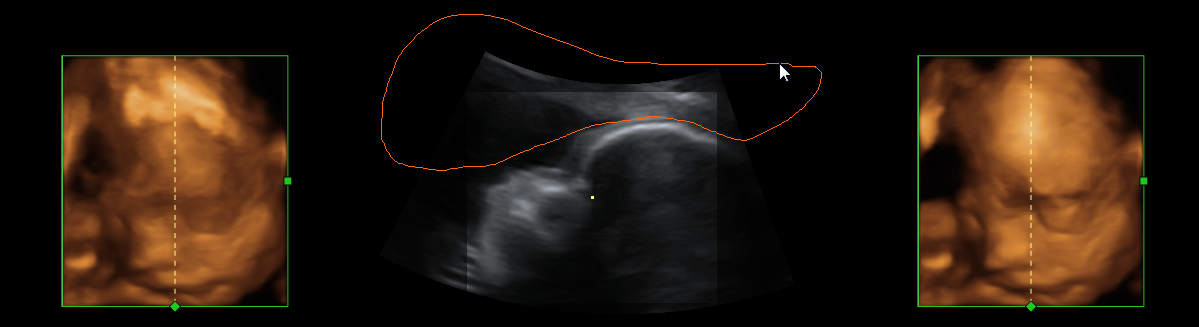

Another taxonomic scheme for ultrasound visualization is based on the different types of data the technique utilized. 3D Freehand and 4D ultrasound, pose very different challenges compared to 2D ultrasound or when handling multiple modalities. Blending b-mode ultrasound for tissue and color-doppler ultrasound for blood flow can be challenging enough in 2D if not in 3D. An example image is shown in Figure 1d. In addition to the ultrasound input, the combination of other medical imaging modalities, such as CT or MRI with ultrasound, provide more information, but also more challenges to the visualization researcher.

Different anatomic regions have different characteristics in ultrasound images, as can be seen in Figure 1. For instance, in a liver scan one might look for tumors using a high-resolution abdominal 2D probe. For heart infarctions, the doctor might need to examine the strain in the heart muscle to detect defect muscle tissue. The wide spread in tissue and pathology difference lead to anatomically specific visualization techniques.

To increase robustness of the ultrasound segmentation, the various approaches are usually tailored for specific anatomies. Carneiro et al. have developed an automatic technique for segmenting the brain of a fetus carneiro08 . By first detecting the cerebellum, the system can narrow down the search for other features. On the other hand, segmentation is an extremely critical procedure which may obscure diagnostically relevant aspects of the anatomy under examination. Consequently, fully automatic segmentation techniques have not been implemented in clinical systems so far, with the exception of a method for follicle volumetry deutch09 , as shown in figure 3.